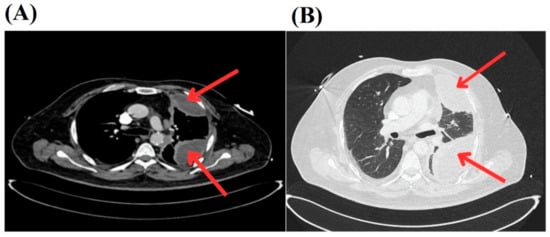

A subsequent chest CT scan revealed a “loculated empyema in the left hemithorax with a small air component, causing near-total collapse of the lower lobe and partial collapse of the upper lobe, with suspicion of an associated bronchopleural fistula” (see Figure 1).

Chest CT images showing loculated empyema in the left hemithorax. (A) The red arrows indicate a loculated empyema with a small air component in the left hemithorax, resulting in near-total collapse of the lower lobe and partial collapse of the upper lobe. (B) The red arrows point to a loculated empyema in the left hemithorax with suspicion of a bronchopleural fistula, as evidenced by air pockets and fluid collection.